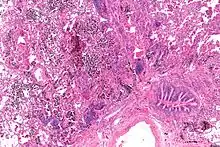

| Micrograph showing a pulmonary hemorrhage. H&E stain. | |